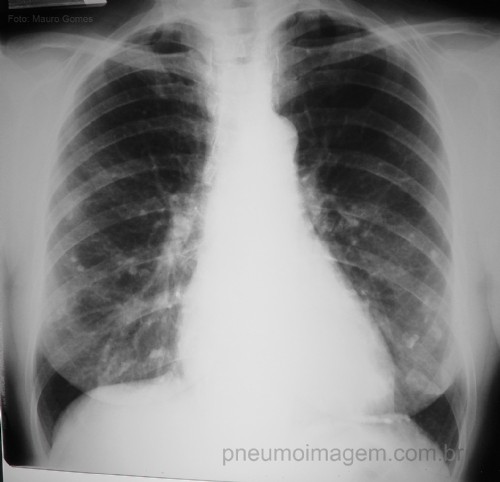

CASO CLÍNICO #14Homem, 55 anos, trabalhador da construção civil, possui dispnéia aos grandes esforços e apresentou o RX de tórax abaixo em exame médico periódico. Qual a principal hipótese diagnóstica? Deixe seus comentários abaixo.

Man, 55 years-old, construction worker, has dyspnea on exertion and the following chest radiography in periodic medical examination. What is the main diagnostic hypothesis? Let your comments below.